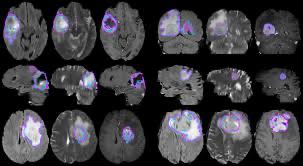

BraTS 2015 Brain Tumor Image Segmentation Dataset

BraTS stands for brain tumor segmentation, which is a dataset about brain tumor image segmentation. The dataset includes MRIs of 220 high-grade gliomas (HGG) and 54 low-grade gliomas (LGG). The four MRI modes are T1, T1c, T2, and T2FLAIR. The segmented "reference standard" provides information about four intratumoral categories, namely edema, enhancing tumors, non-enhancing tumors, and necrosis.